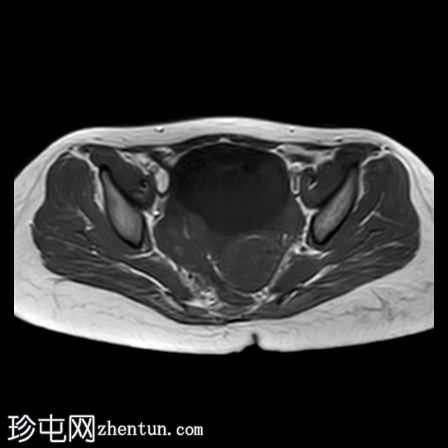

轴位

T2加权像

右侧卵巢增大,卵泡呈周边排列。

附件血管蒂扭转(漩涡征)。

右侧附件旁可见一较大的、边界清晰的盆腔囊性病变,向右倾斜,提示为卵巢旁囊肿。

本病例展示了卵巢扭转的典型影像学特征,包括卵巢增大、卵泡呈周边移位、卵巢向内侧偏移以及特征性的漩涡征。

在这种情况下,较大的卵巢旁囊肿被认为是发生卵巢扭转的高危因素。如果卵巢旁囊肿较大(>5厘米)或活动度较大,其重量/活动度增加会牵拉附件,导致卵巢和输卵管发生扭转。